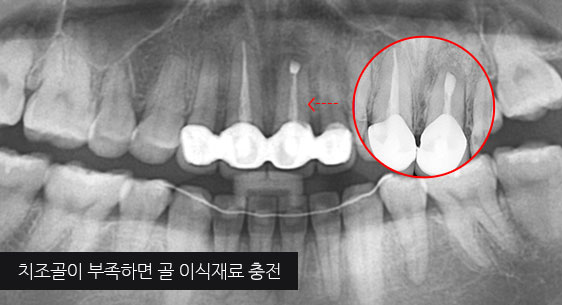

심한 염증으로 치조골이 광범위하게 소실, 아래쪽 신경관이 가까이 있어 치근단수술이 불가능한 상태, 타 병원에서 임플란트 진단을 받았지만,

고운미소치과에서 치아를 발치하고 뿌리 쪽 염증을 제거한 후 발치한 치아를 다시 심는 치아재식술을 시행하였습니다.

기존 신경치료 부위에 염증과 치조골이 소실되고 있는 상태

치아를 발치하고 염증을 제거, MTA로 충전하고 치아를 다시 심음. (난이도 중)